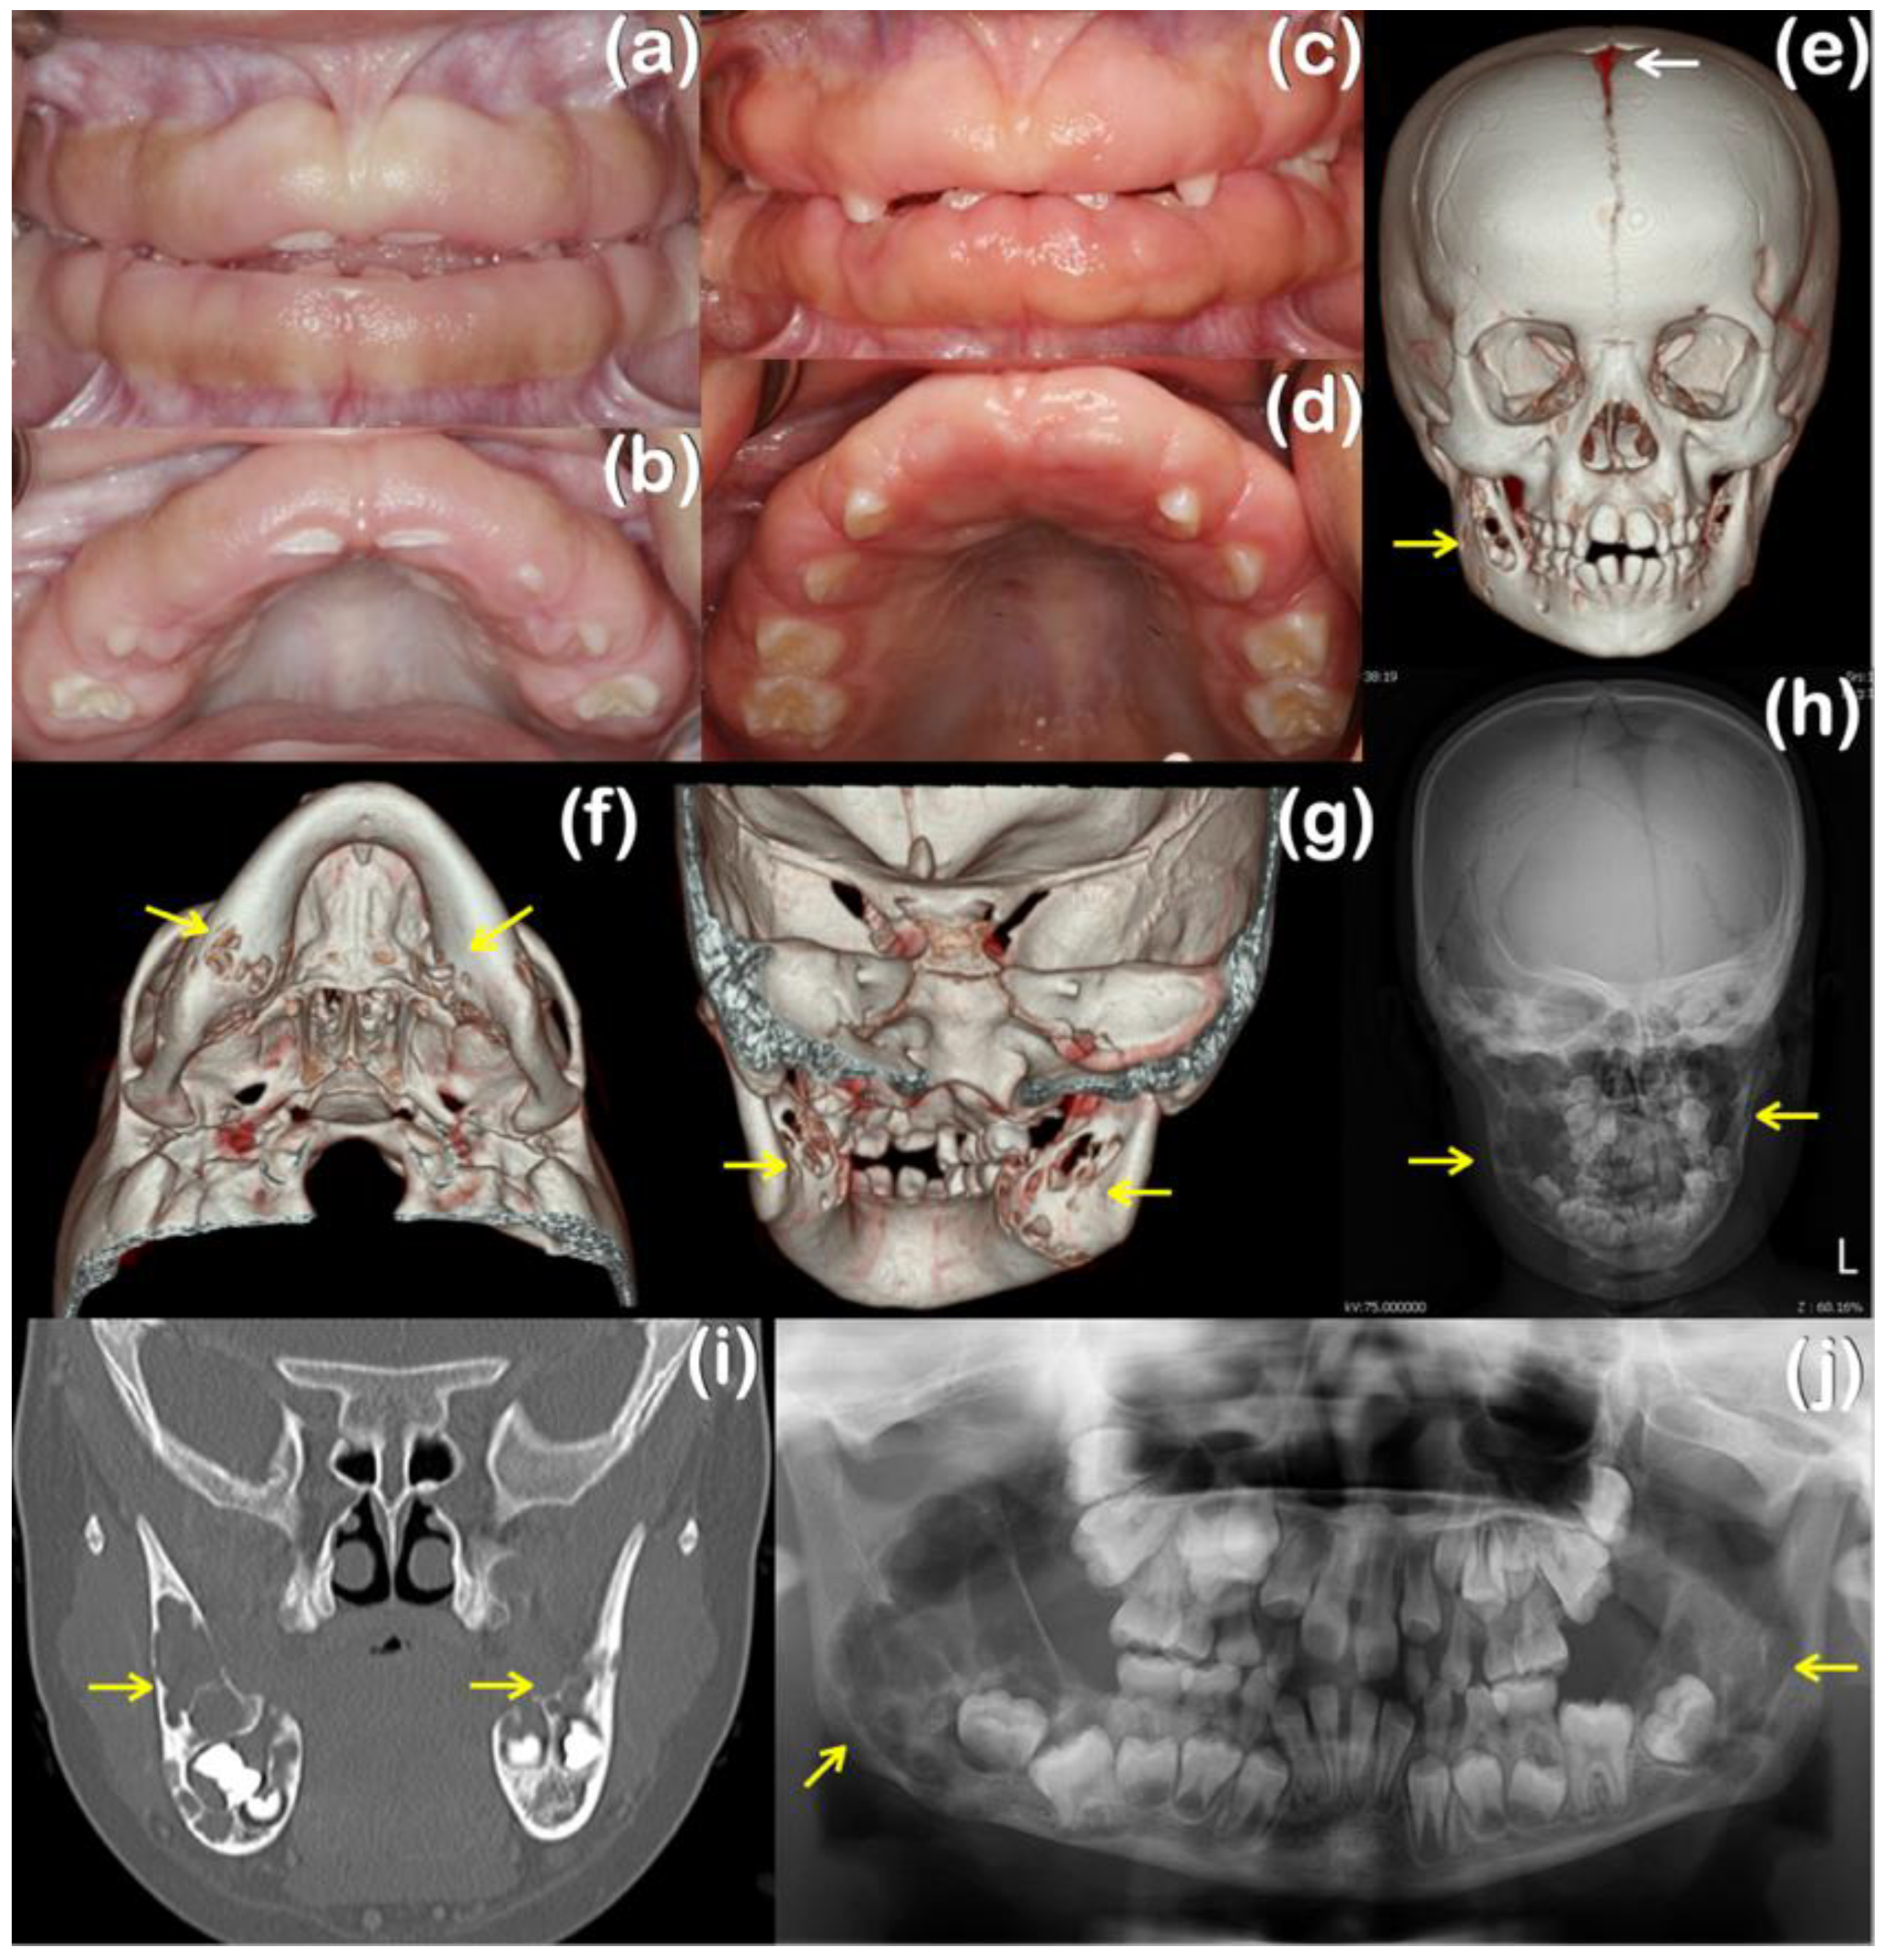

| 1 | 1 (Female) | Ramon Syndrome | Gingival fibromatosis, cherubism-like lesions, a persistent open anterior fontanelle, focal epilepsy, left eye amblyopia | TBC1D2B variant NM_144572.2; NP_653173.1 c.1879_1880del p.Glu627LysfsTer61 chr 15-78305554-TTC-T Novel | MutationTaster: Disease causing Prob = 1 PolyPhen-2: N/A SIFT: Damaging; score = 0.858 CADD: N/A DANN: N/A Varsome: N/A |

| 2 | 2 (Male) | Hereditary gingival fibromatosis | Gingival fibromatosis | TBC1D2B variant NM_144572.2; NP_653173.1 c.2471A>G p.Tyr824Cys chr 15-78295750-T-C rs199928887 MAF = 0.00001301 KREMEN2 variant NM_172229.3; NP_757384.1 c.892C>T p.Arg298Cys chr 16-3017162-C-T Novel | MutationTaster: Disease causing Prob = 0.999153978449563 PolyPhen-2: Probably damaging; score = 0.999 SIFT: Damaging; score = 0.01 CADD score = 22.8 DANN score = 0.9935 Varsome: Uncertain Significance MutationTaster: Disease causing Prob = 0.876965507429932 PolyPhen-2: Probably damaging; score = 0.994 SIFT: Tolerated; score = 0.18 CADD score = 23.5 1 DANN score = 0.9981 2 Varsome: Uncertain significance |

| 3 (Male) | Hereditary gingival fibromatosis | Gingival fibromatosis, epithelial dysplasia, dense mandibular bone | |||

| 4 (Male) | Hereditary gingival fibromatosis | Gingival fibromatosis, dense mandibular bone |